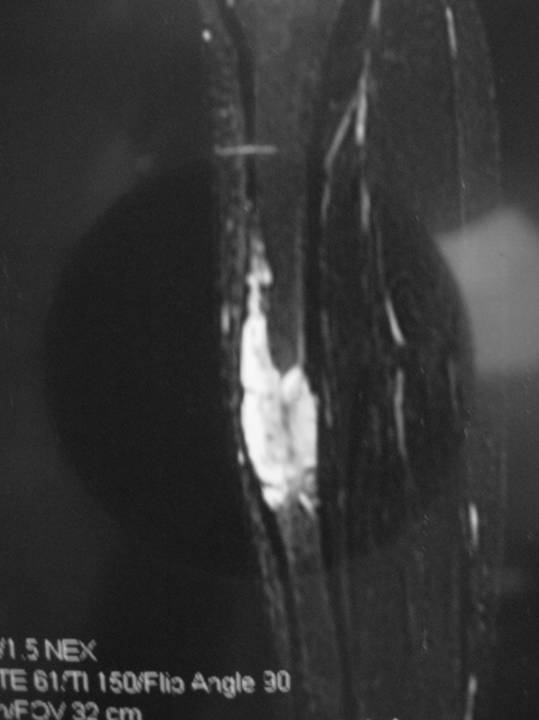

Radiographic Presentation

- Sharply defined osteolytic defect (lobulated, multicystic, or “soap bubble”)

- May be considerable perilesional sclerosis